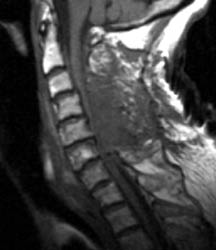

75 y.o. female with about a two-year history of continued gait abnormalities and decreased dexterity. On examination her strength was normal, however, she had bilateral Hoffmann signs as well as bilateral Babinski signs. Her strength was 5/5 but her gait was ataxic. Magnetic resonance imaging showed severe stenosis at C3, C5 and C6 levels. She underwent C3-C6 laminectomies.

Immediately post-operatively she did well, however, within 36 hours of the operation, she slipped and fell due to spilled milk on the floor . After that injury, the patient was neurologically intact. However, on postoperative day #2 for morning rounds, the patient was noted to be confused and weakened on the left side, both arm and leg, leg more than the arm. An immediate CAT scan of the brain and cervical spine was obtained. Immediate MRI was also obtained.

Non-enhanced sagittal T1 (A), sagittal T2 (B) and axial T1 images demonstrate a large fluid collection, predominantly low signal on T1, bright on T2 with a few areas of T1 hyperintesity mixed within. These constellation of findings are consistent with a post-operative epidural hematoma with blood products of various ages. There is severe severe spinal canal stenosis at C3-4, and very severe spinal canal stenosis at C4-5 and C5-6. The cord is markedly flattened in the anterior-posterior dimension, to approximately 2-3 mm secondary to mass effect from this fluid collection. There is abnormal T2 weighted hyperintensity within the substance of the cord at the C5-6 and C6-7 levels, consistent with some edema.